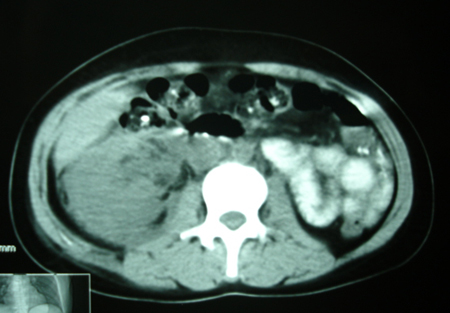

以下是引用bmw011在2009-4-23 13:28:00的发言:[br]考虑右肾包膜下血肿。

以下是引用卜一在2009-4-23 15:43:00的发言:[br]考虑右肾包膜下血肿,不排除占位病变伴出血可能,建议进一步检查。